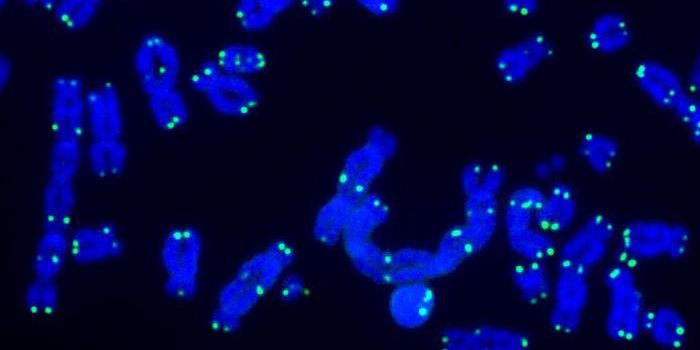

FEB 12, 2025Genetics & GenomicsHuntington's disease is a neurodegenerative disorder that is usually fatal about 15 to 20 years after a patient is diagn ...

FEB 10, 2025Genetics & GenomicsThe human genome can have some quirky features, like copy number variation. When this happens, an individual carries, or ...

JAN 20, 2025Genetics & GenomicsResearchers have made a major breakthrough in our understanding of Huntington's disease. This genetic disorder has long ...